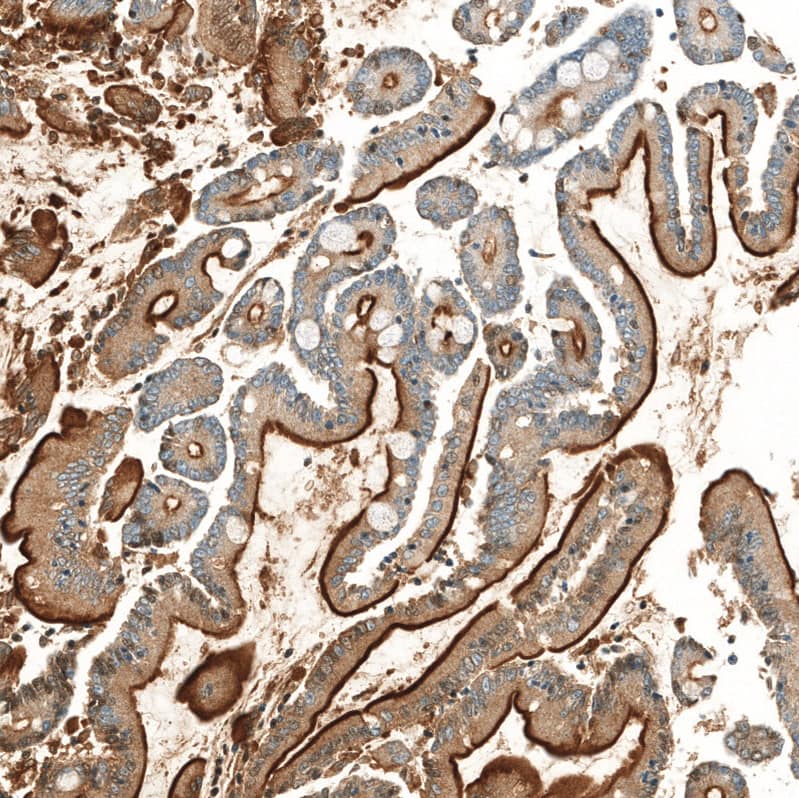

Staining of human small intestine shows strong apical membranous positivity in glandular cells.